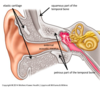

external ear

from auricle to tympanic membrnae via external acoustic meatus

collect and convey sound waves to tympanic membrane

middle ear

from tympanic membrane to oval window and esutachian (auditory) tube

amplifies and conducts sound waves to internal ear

internal ear

from oval window to internal acoustic meatus

converts special sensory information - into fluid waves, then APs which are conducted to the brain

tympanic membrane and EAM sensory nerve supply

CNV3 (superior part of EAM and tympanic membrane) and CNX (inferior part of EAM and TM)

where does the EAM extend from

deeper part of concha to tympanic membrane